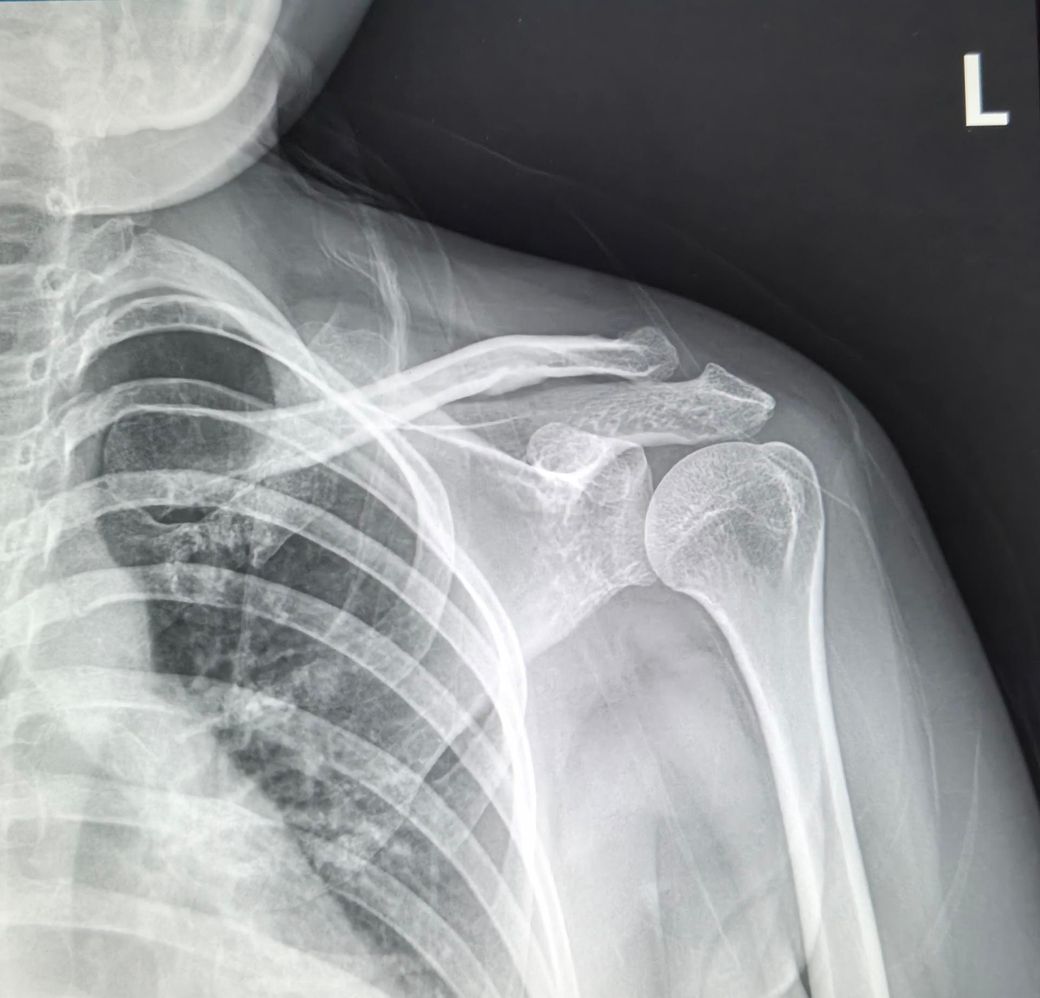

2024년도에 전동차가 전복되면서 왼쪽어께 다치면서 어께가 많이 안좋아요.

2025년10월14일 찍은 오른쪽,왼쪽어께사진이랑

2026년2월19일 목요일 오른쪽,왼쪽어께사진이랑

비교해주세요.왼쪽어께가 찌릿하고 통증있어요.

2025년도 찍은거랑 2026년 찍은거랑 차이 많이 나보이죠?

• 1번 째 사진

비교해보면 뼈의 정렬이나 관절간격,건봉모양 같은 기본부조는 크게 달라진 부분이 없어보입니다. 짧은시간사이에 관절이 급격히 닳았다거나 뼈가 무너졌거나 하는 진행성 변화는 뚜렷하지 않습니다. 다만 원래부터 견봉아래 공간이 약간 좁은 구조라서 회전근대 힘줄이 지나가는 공간이 넉넉한 편은 아니고,이런 해부학적 형태는 시간이 지나면서 염증이나 충돌증상이 반복될 가능성은 있습니다. 마지막 MRI 단면을보면 회전근개 힘줄부위에 염증또는 부분손상으로 의심되는 신호변화가 보입니다.염증,부분파열 또는 퇴행성 변화기능성이 있습니다. 이런경우 팔을 90도이상 올릴때 통증이 심해지는 양상이 흔합니다. 빠른쾌유를 빕니다!

오른쪽은 비교적 차이가 없지만 왼쪽은 살짝 차이가 있습니다.

다만 엑스레이 촬영시 자세적인 문제, 통증에 의한 근육 사용패턴 문제 등 차이가 날 수 있기에 좀 더 정확한 소견은 전문의에 판독을 들어보시길 바랍니다^^

사진만으로 보면 "2025년 대비 2026년 X-ray에서 뼈 위치가 크게 변했다거나 탈구.골절이

새로 생긴 차이는 뚜렷하지 않습니다."

다만 X-ray는 "근육.힘줄.회전근개.신경 문제를 거의 못 봅니다" 찌릿한 통증은 이런 연부조직/신경 원인이 흔해요.

전동차 전복 외상 병력이 있고 통증 지속이면 "회전근개 손상, 충돌증후군, 경추 연관통" 가능성 있습니다.

“차이가 많이 난다”기보단 "X-ray로는 한계가 있고, MRI가 꼭 필요한 상황"으로 보입니다.